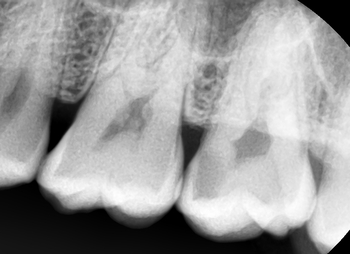

눈으로 봤을 때는 비쳐보이는 듯하면서 안비쳐보이는 거 같기도 하고...

그래서 저희치과는 검진 할 때 개개인의 상황에 따른 주기대로 파노라마를 찍는 것을 권해드립니다.

눈으로 보는 검진만 하면 충치를 놓치게 되면 이 동기처럼

어느순간 봤는데 충치가 너무 심해져 있어

신경치료+크라운으로 가는 대참사가 벌어질 수도 있으니까요.